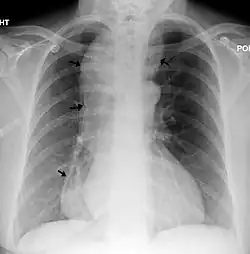

![]() | |

| A chest X-ray showing achalasia (arrows point to the outline of the massively dilated esophagus) | |